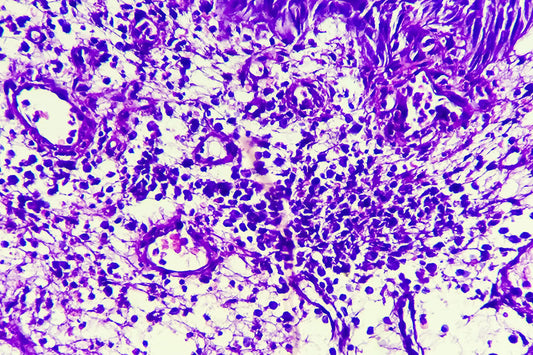

猫とIBD - ステロイドが効かない時に腸内では何が起きているのか?

人間のみならず、近年では猫においてもIBD(もしくはIBD疑い)の診断が増えています。ここでは腸内細菌解析の現場の視点から、猫のIBD、そしてステロイドが効かなくなる背景について記載します。